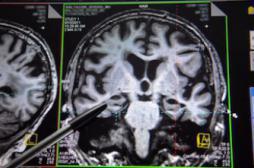

LES MALADIES

SYMPTÔMES